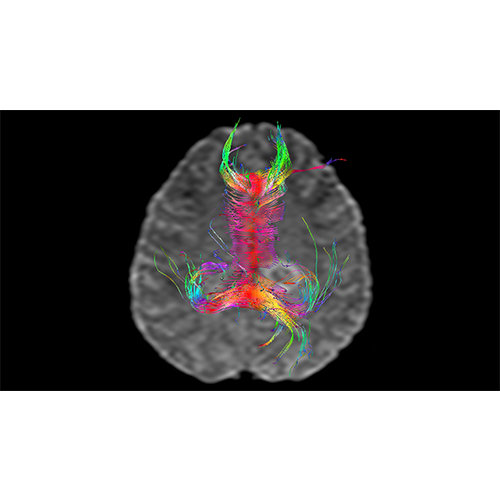

View X-Ray CT & MRI Scans Fast and Easily

High-quality and fast 3D reconstruction and 3D rendering

Designed mainly for CT and MR DICOM modalities.

Performs 3D reconstruction and volume rendering.